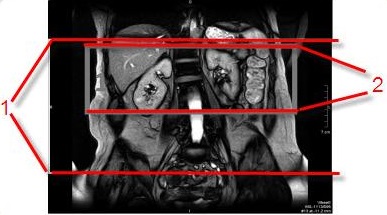

Figure 8. Coronal localizer with IR band and resultant coronal abdominal veins

Table 6. Image legend

NumberDescription

1Coronal localizer with axial IR band (red box) applied over the heart to saturate arterial flow.

2Resultant Inhance Inflow IR coronal image of abdominal veins.